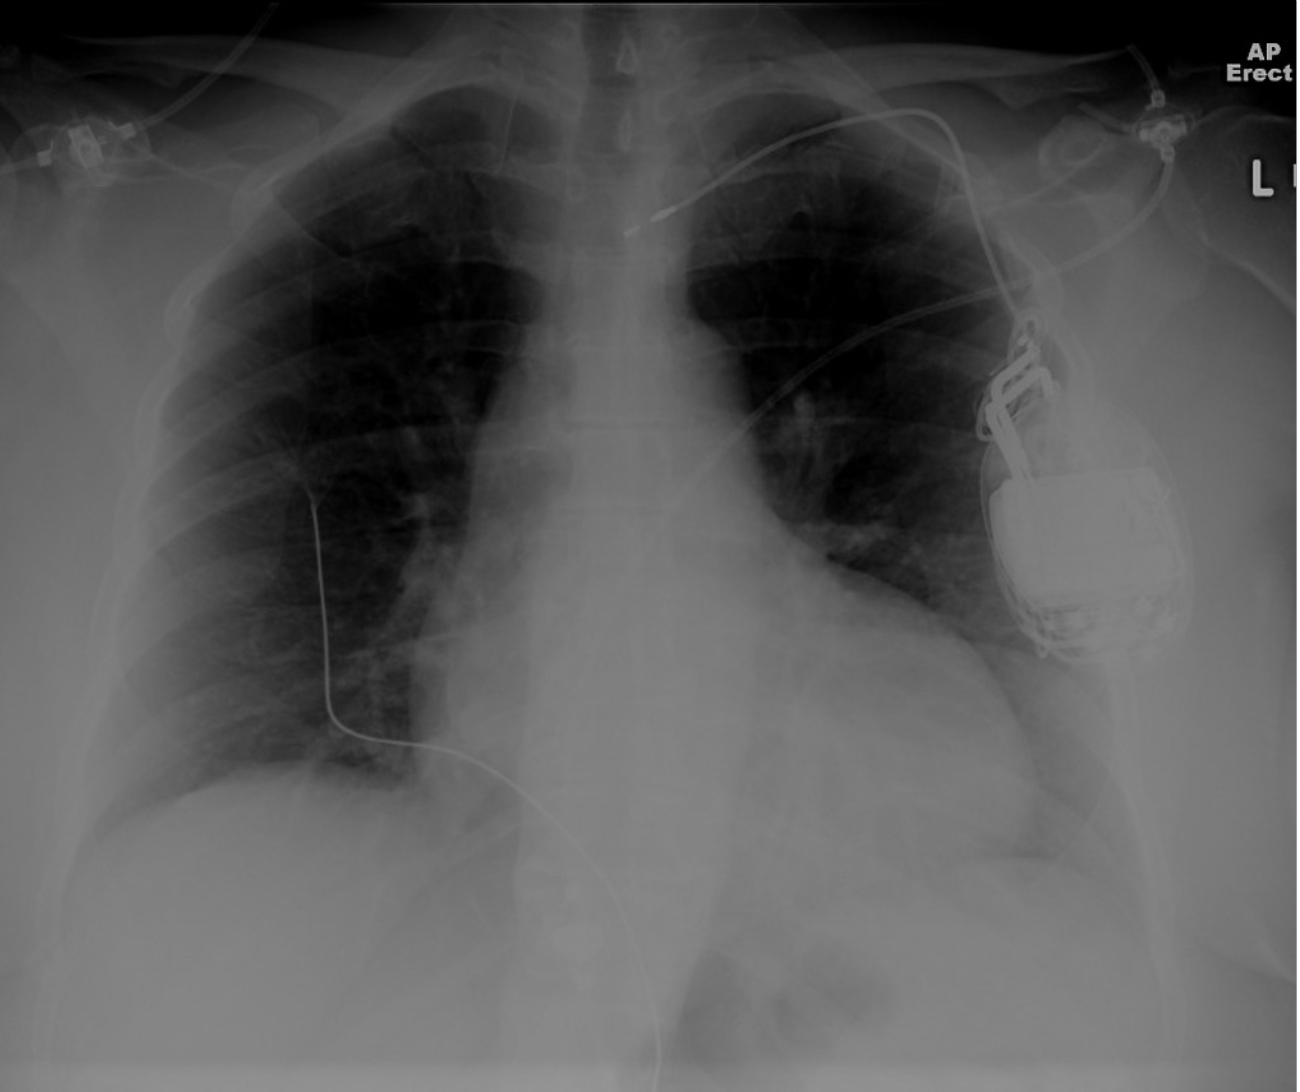

Single lead pacemaker, retracted (Twiddler)